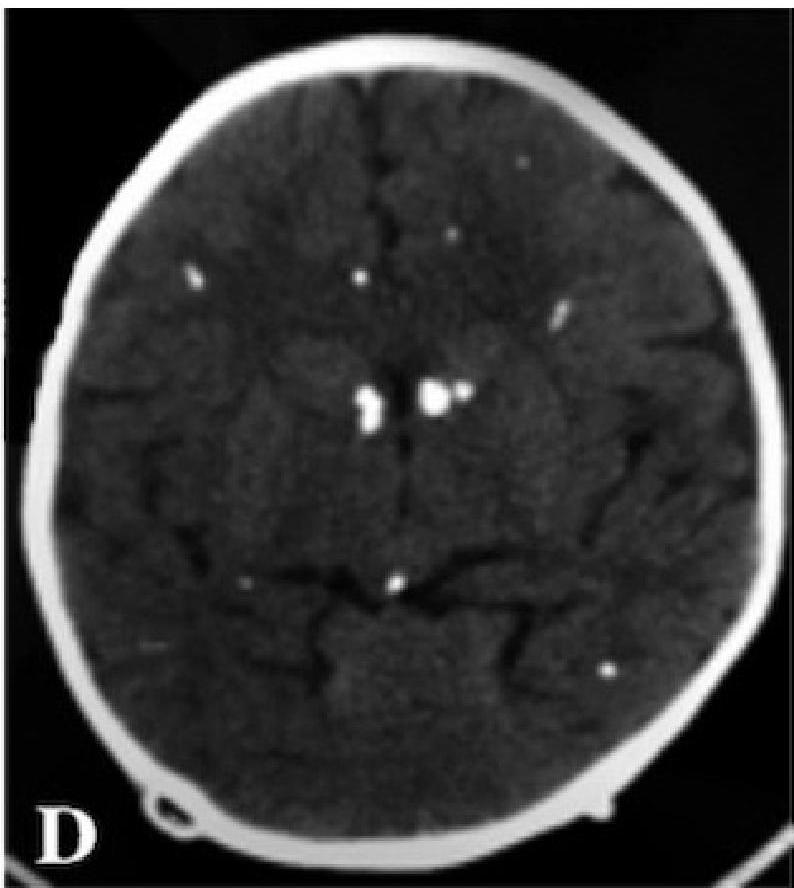

- Leads to: Inflammation, Cellular destruction, Calcification (especially in periventricular areas of the brain).

- Neurological: Microcephaly, Seizures, Intracranial calcifications (classically periventricular).

Ventriculomegaly and calcification of congenital CMV

- Imaging: Cranial ultrasound/CT → periventricular calcifications, ventriculomegaly.